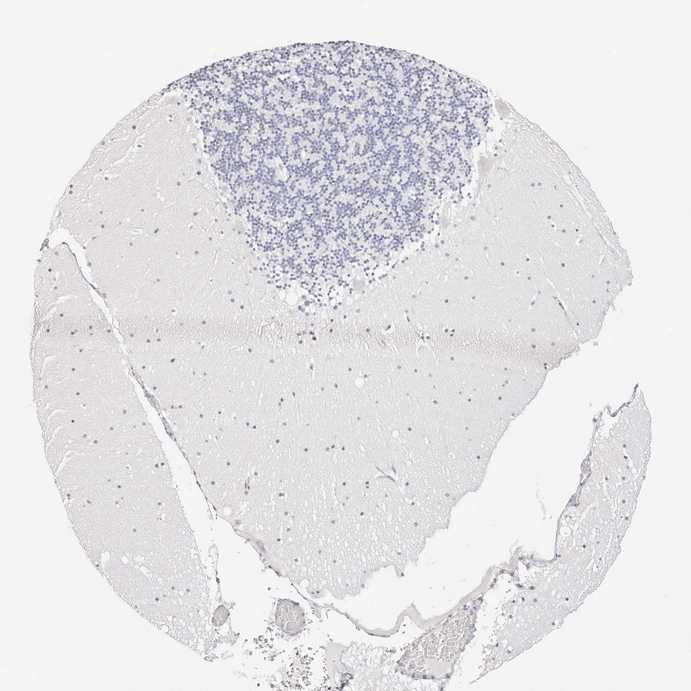

CEREBELLUM - Antibody stainingi

Antibody staining in the annotated cell types in the current human tissue is reported as not detected, low, medium, or high, based on conventional immunohistochemistry profiling in selected tissues. This score is based on the combination of the staining intensity and fraction of stained cells.

Each image is clickable and will lead to virtual microscopy that enables deeper exploration of all samples and also displays staining intensity scores, fraction scores and subcellular localization as well as patient and tissue information for each sample.

Antibody HPA029874Antibody CAB015949Antibody CAB016522

Purkinje cells Not detectedNot detectedMedium

Cells in granular layer Not detectedNot detectedNot detected

Cells in molecular layer Not detectedNot detectedNot detected